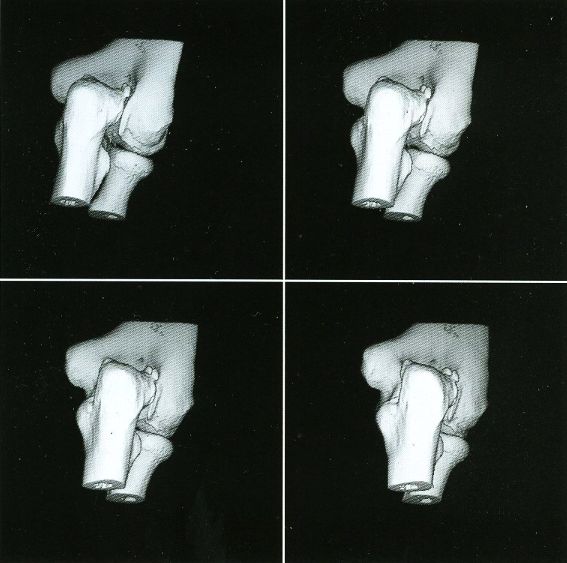

Here are typical examples of VoxelQ displays. These are mostly only windows, not the full screen which is more along the lines of the last block of AcQSim photos.

VoxelQ Shaded Surface

While the VPP and Voxelscopes I and II rendered "back-to-front" to implement hidden surface removal, the redesigned VoxelQ hardware was optimized for ray tracing with volume rendering capabilities. VQ projected a ray from each pixel on the display back through the object and was able to perform computations along the way. An innovative sub-voxel search algorithm rendered much more realistic surfaces using relatively simple surface shading algorithms. Even Anthony was impressed with the image quality when this technique was first simulated in software with the intent of incorporating it into the microcode - and he was most familiar what else was being done in software, which could render the best images since there were fewer time constraints. In addition to hidden surface removal and gradient shading, this approach supports various forms of transparency with perspective enabling the simulation of X-ray views ("reprojection") as well as rendering translucent organs. Many of the changes were implemented in microcode with relatively small changes to the actual hardware. But the key innovation that differentiated VoxelQ from the machines before it was the "Object Resampling Memory" (ORM) which generated tri-linearly interpolated voxel data based on full 3-D coordinates. Essentially, the eight adjacent voxels closest to the specified coordinate in the original dataset were accessed simultaneously and an interpolated result was computed auto-magically. For successive coordinates that were close together (as they would be for ray tracing), the effective throughput could approach 10 million tri-linearly interpolated voxels per second. The ORM was the only totally new custom board and replaced the MicroVAX memory.

Shading of the rendered objects is essential to the perception of 3-D depth in a static display of a single image (no stereo). Motion parallax also contributes to this but only if the update rate is high enough. The VPP only had "depth shading", whereby each pixel's value was modified by distance from the viewer. Subsequent machines used "gradient shading" which also calculated the local rate-of-change of the surface to modulate the pixel intensity. While this was not photo-realistic, the overall effect was quite satisfactory at a much lower computational cost. And with the tri-linearly interpolated voxels, the result was actually quite impressive.